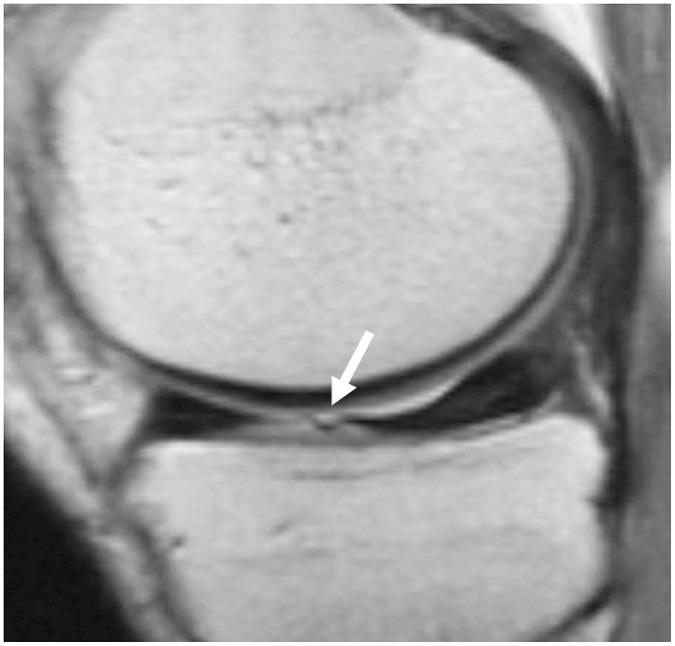

To accurately interpret knee MRI, it is important not only to know the basic meniscal anatomy but also to distinguish it from that under pathological conditions. Thus, it would be helpful to know the normal meniscus variants (false positives) that could be mistaken for meniscal tears, and tears that could easily be missed and incorrectly diagnosed as normal (false negatives). False positives include synovial recesses, meniscal flounce, the relationship between the popliteus tendon and lateral meniscus, transverse ligament, the anterior root of the meniscus, and meniscofemoral ligament. False negatives include focal radial tears, flap tears, posterior root tears, meniscocapsular separation, and discoid meniscal tears. In this pictorial essay, we reviewed the imaging data obtained in the aforementioned cases.